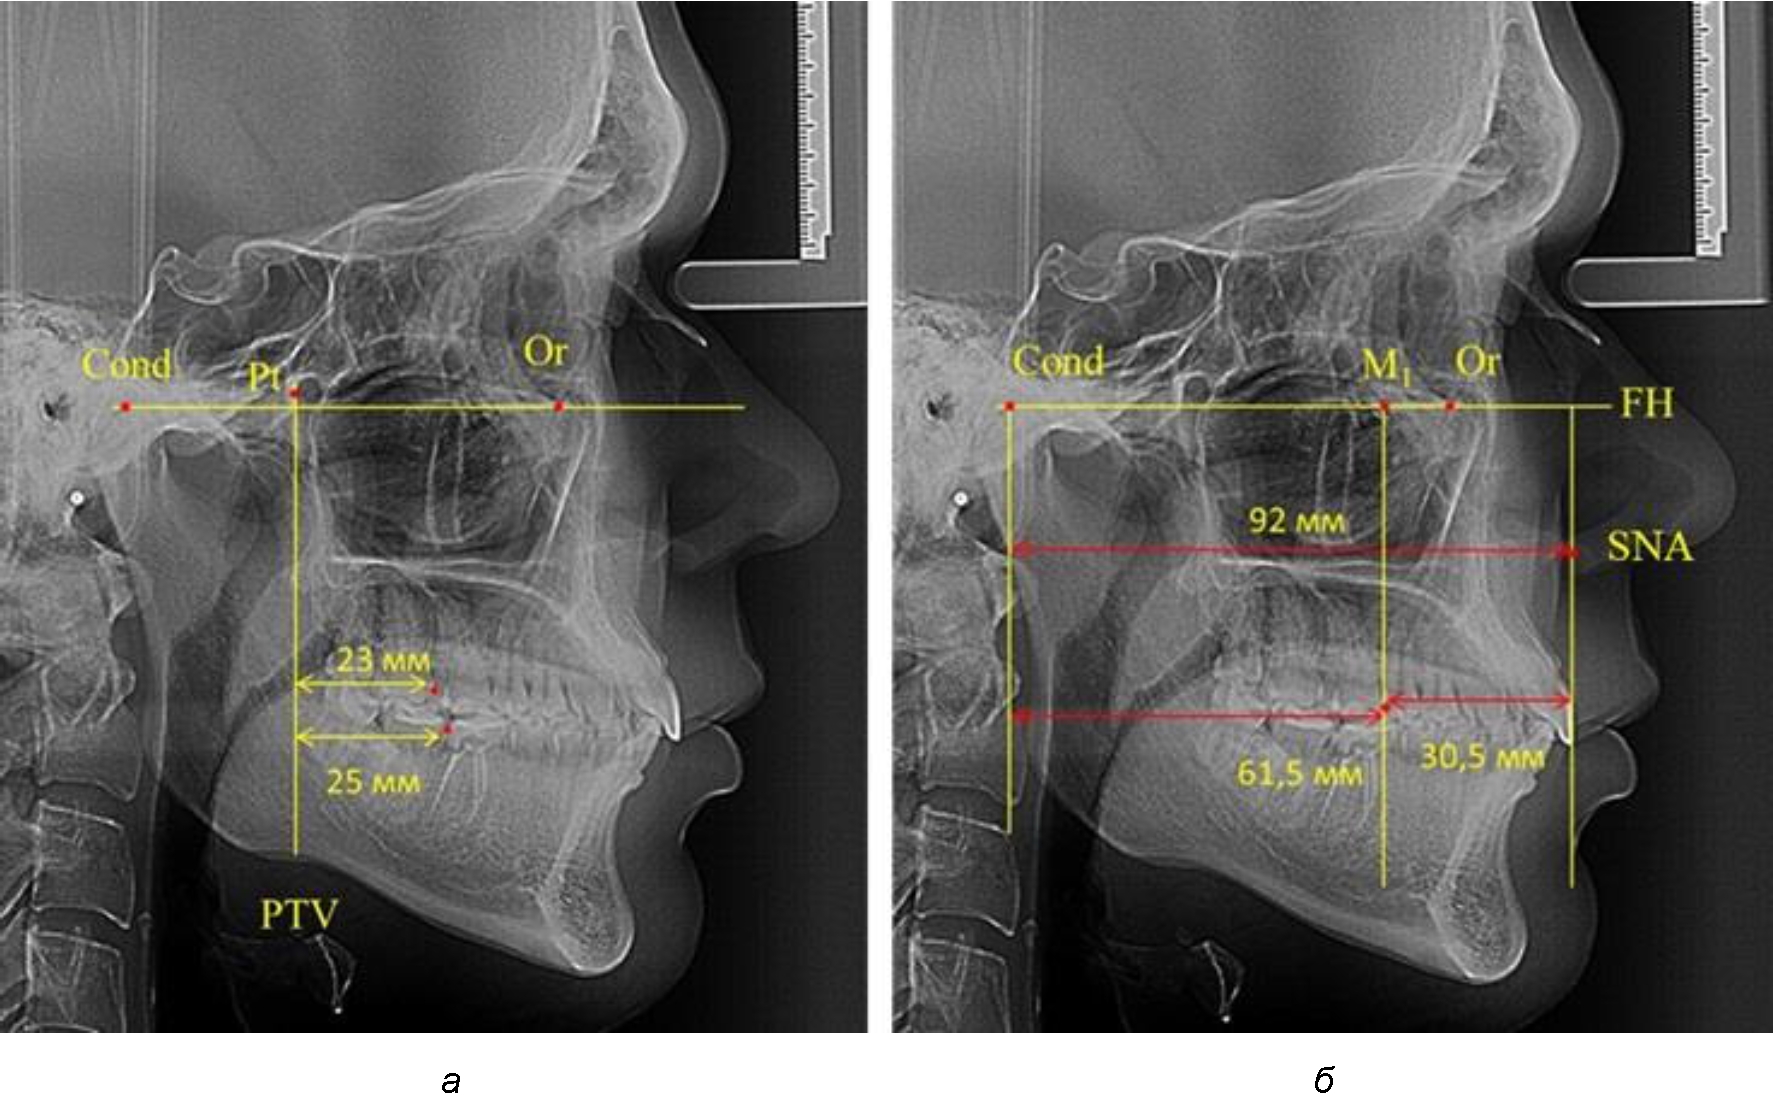

При проведении анализа к Франкфуртской горизонтали проводили передний и задний перпендикуляры. Передний спинальный перпендикуляр проходил через выступающую точку передней носовой ости (spina nasalis anterior – SNA), а задний суставной перпендикуляр опускали из кондилярной точки Cond. Молярный перпендикуляр проводили через медиальную поверхность первого постоянного моляра. Указанная вертикаль отделяла замещающие зубы постоянного прикуса от добавочных зубов (постоянных моляров), что вполне логично для анализа положения первых постоянных моляров в гнатическом комплексе (рис. 1).

Рис. 1. Метод определения положения первых верхних моляров по Ralph E. McDonald (а) и по предложенному методу (б)